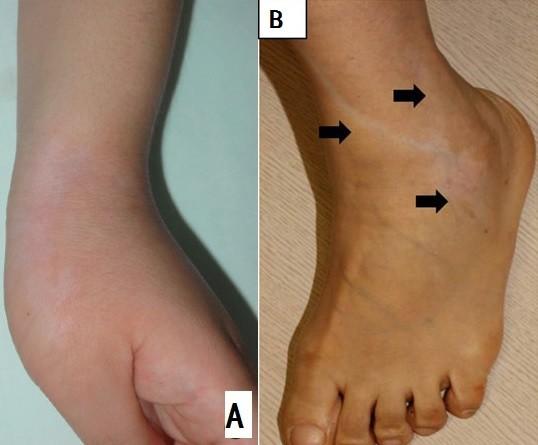

激素导致色素减退的资料非常少,有几例是治疗腱鞘炎使用激素封闭后(下图标识A),或者使用皮肤破损处注射后,出现色素减退的现象,有1例是外用激素膏后导致的皮肤呈现出线性的色素减退(下图标识B)。

上图A是腱鞘炎,使用激素封闭后2月出现的色素减退。上图B为64岁女性,使用高强度激素涂抹湿疹处,1月后出现的线性的色素减退,出处见参考文献3。

关于外用激素导致的色素减退,具体原因不清楚,考虑可能是外用激素可以通过抑制涂抹处表皮细胞中的前列腺素或细胞因子,产生来改变黑素细胞功能,导致色素减退。形成线型的色素减退,可能和激素经皮肤涂抹部位或者注射部位沿淋巴管扩散,从而影响黑素细胞的功能产生色素减退。

使用外用激素药膏涂抹或者激素注射后导致的皮肤色素减退,通常也得连续使用中-强效激素后1-3月才能出现,并且外用药膏后出现这种改变,仅看到1例。所以如果你的宝宝使用就1周激素,出现的色素减退的表现,就不要怪罪于激素啦。